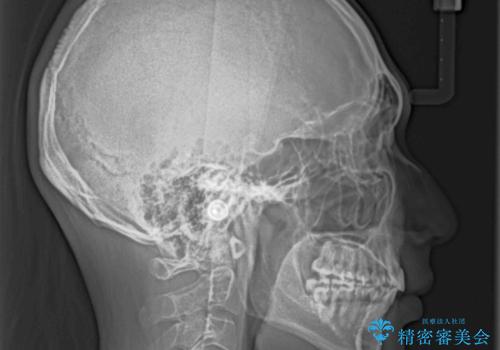

- 前歯の叢生と八重歯を気にして来院された患者様です。

叢生が強く、奥歯の咬合も左右差が大きかったため、上下左右4本を抜歯して、ワイヤー矯正を行うこととしました。

奥歯の咬み合わせを改善したいため、治療期間が長くなりましたが、患者様には辛抱強くお付き合いいただきました。

上下の正中を合わせることもでき、患者様には大変満足していただきました。